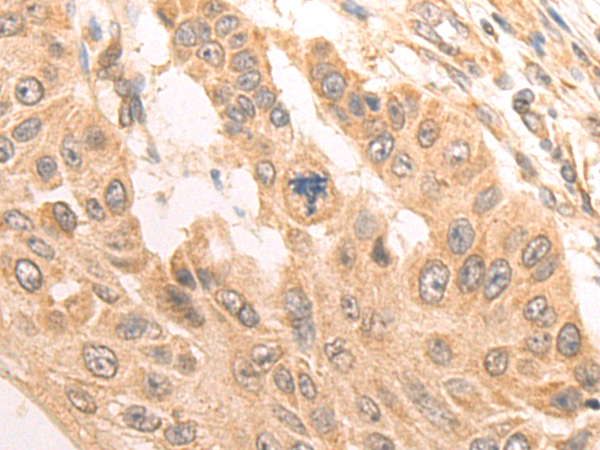

分类: 科研抗体货号: P08539别名: Bex; NADE; HGR74; NGFRAP1; DXS6984E应用: IHC反应种属: Human